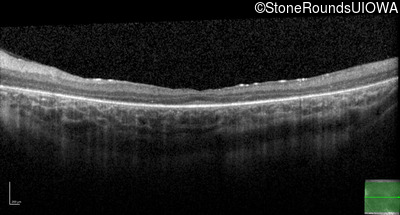

Age at visit: 13 years